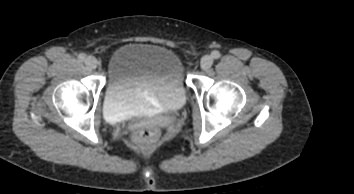

Мультиспиральная КТ мочевого пузыря является частью протокола обследования органов малого таза. Это высокоинформативный рентгенологический метод исследования, позволяющий детально визуализировать мочевой пузырь, нижнюю часть мочеточников, внутренние половые органы, прямую кишку.

Зачастую подобное исследование проводится при мочекаменной болезни (МКБ) для выявления конкрементов, определения их положения, размеров и плотности. Локализация конкремента существенно влияет на терапевтическое лечение МКБ, а наличие дивертикулов стенки мочевого пузыря на возможность самостоятельного выхода камня.

Также при данном исследовании возможно выявить утолщение стенки мочевого пузыря, что при диффузных изменениях может соответствовать проявлениям цистита, а локальные или неравномерные утолщения – характеризовать патологический процесс обусловленный новообразованиями.

Для улучшения визуализации патологических образований, в частности, при подозрении на опухолевый процесс, проводится внутривенное болюсное контрастирование. Методика контрастного усиления основана на введении в вену контрастного препарата, который в большей степени накапливается в патологически измененных участках и обеспечивает их яркую визуализацию на фоне здоровых тканей. Контрастирование дает возможность определить врачу границы опухоли, оценить степень прорастания в соседние органы и ткани, выявить опухоли минимальных размеров (как первичного, так и метастатического характера).

Мультиспиральная КТ используется для диагностики аномалий развития мочевого пузыря, травматических повреждений, воспалительных заболеваний и опухолевых процессов органов малого таза. Преимуществами данного исследования является высокая скорость сканирования и доступная цена. Однако в ряде случаев может быть более предпочтительно выполнение магнитно-резонансной томографии, которая обладает высокой чувствительностью и информативностью для обследования органов и мягких тканей малого таза. В клинике «Доступная медицина» обследование мочевого пузыря входит в протокол МРТ малого таза и его можно пройти на нашем современном оборудовании экспертного уровня